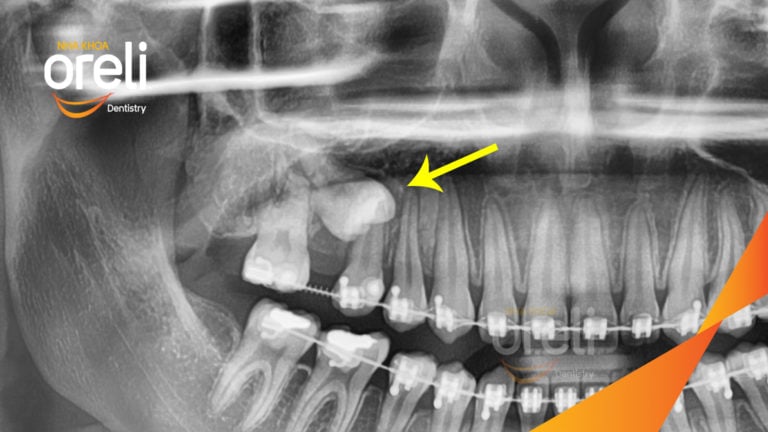

Tháo mắc cài ca niềng răng sai khớp cắn hạng 3 không nhổ răng tại Oreli

Ca niềng răng sai khớp cắn hạng 3, cắn chéo chen chúc răng cửa, mất răng 6 hàm dưới, răng…